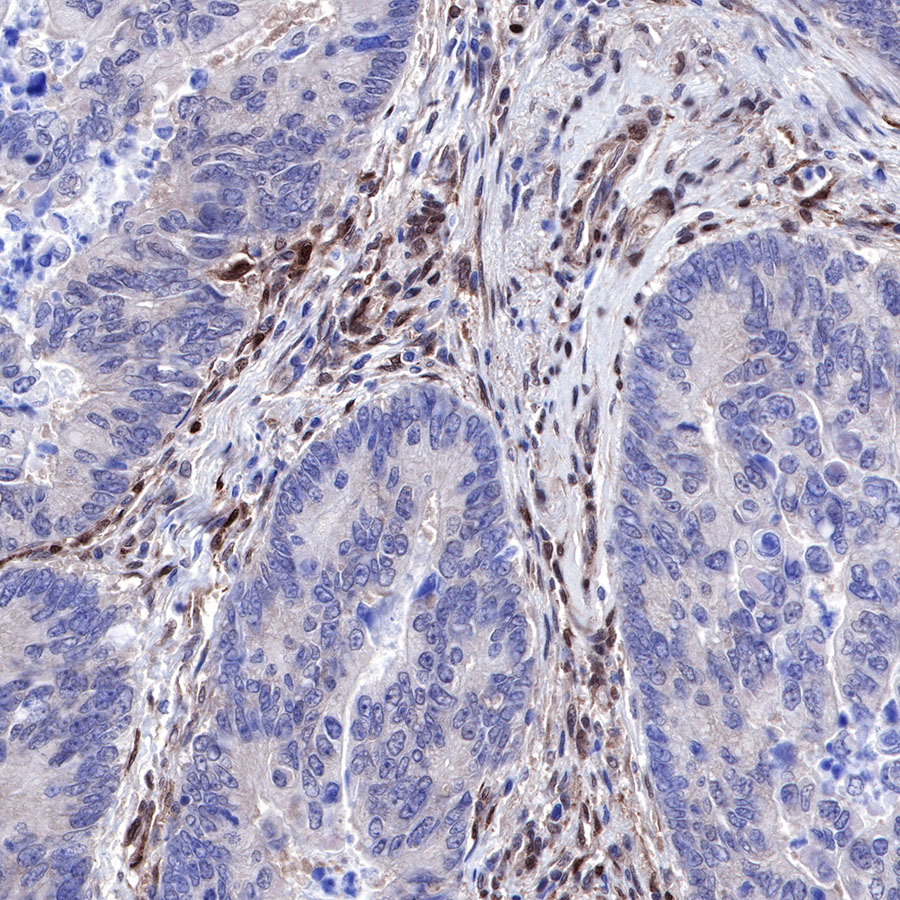

Immunohistochemistry

IHC shows positive staining in paraffin-embedded human colon cancer. Anti-PTEN antibody was used at 1/500 dilution, followed by a HRP Polymer for Mouse & Rabbit IgG (ready to use). Counterstained with hematoxylin. Heat mediated antigen retrieval with Tris/EDTA buffer pH9.0 was performed before commencing with IHC staining protocol.